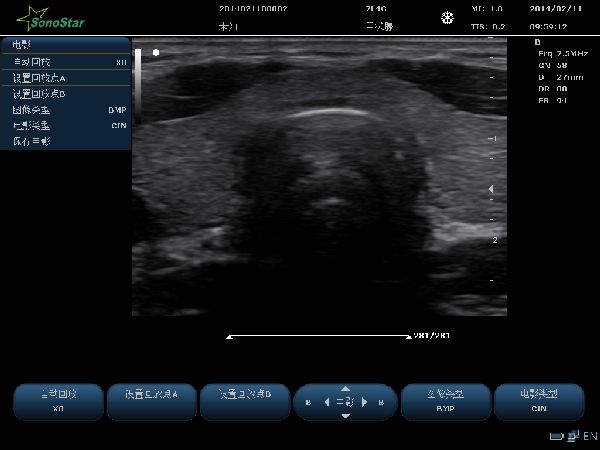

C10M 便携式彩超B超彩超超声诊断仪多普勒

技术参数:1.设备用途说明用于腹部、心脏、妇科、产科、泌尿科、小器官、儿科、血管等方面的检查。2.主要技术参数及功能:2.1技术平台:★linux +ARM+FPGA2.2通道数、阵元数★物理通道数:

用于腹部、心脏、妇科、产科、泌尿科、小器官、儿科、血管等方面的检查。